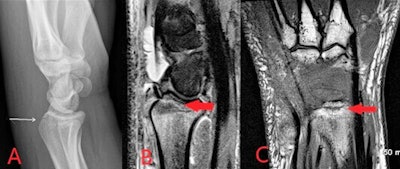

MRI protocols for suspected bone and joint complications of injected drug use should include a fluid-sensitive sequence such as STIR, in addition to T2 or proton density and T1-weighted sequences in at least two planes. Bone marrow edema is the earliest imaging finding identifiable in acute osteomyelitis and appears on MRI as high T2 and STIR signal intensity of the bone with corresponding low T1 signal. Enhancement following contrast administration is also seen.

High T2/STIR signal without low T1 signal is less specific and may represent reactive osteitis rather than osteomyelitis. Cortical bone destruction can be identified as loss of the normal peripheral T1 hypointense cortical rim. Assessment of the extent of the infection in adjacent soft tissues, differentiation of bone from soft tissue infection and surgical planning can also be reliably achieved on MRI, according to the authors.

MRI is extremely sensitive in the detection of septic arthritis, but findings are nonspecific and can overlap with inflammatory arthritis. MRI protocols typically involve T1, T2, fluid-sensitive (such as STIR) and gadolinium-enhanced sequences.

"MRI may be performed where there is diagnostic uncertainty or for the evaluation of surrounding soft tissues and bones," Delaney et al wrote. "MRI will show a joint effusion with synovial thickening and enhancement, indicative of active synovitis. In chronic infections, destruction of the joint surfaces and periarticular structures occurs with resultant deformity and reactive sclerosis."